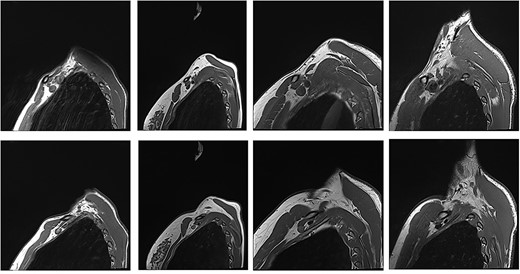

With the arm elevated, there is narrowing of the costoclavicular space between the posterior border of the clavicle and anterior border of the first rib (Figs 1 and 3). In unaffected patients, there is a small amount of fat that persists around the cords of the brachial plexus with the arm elevated (Fig. 2). In our series, we considered a patient to be positive for nTOS if there is loss of the perineural fat signal demonstrating that the nerves are in direct contact with the posterior border of the clavicle and anterior border of the first rib (Fig. 1b).

Patients with nTOS. The top rows are sequences with the arm in the neutral position. The bottom row is the corresponding patient with the arm raised.